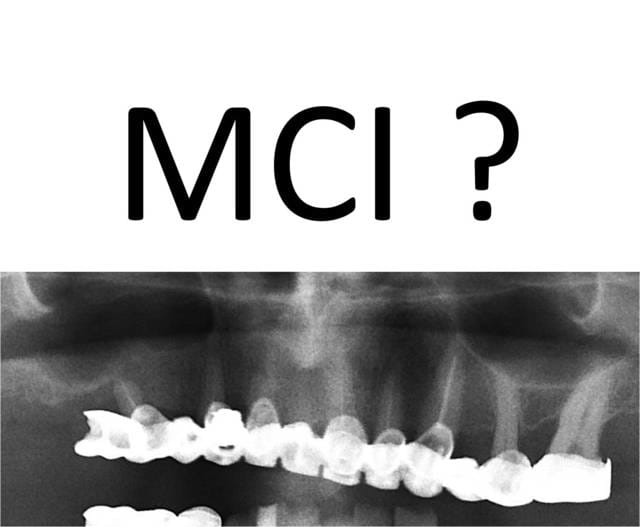

pourquoi mci? il reste suffisamment de racines valables pour supporter un provisoire fixe pendant quelques mois et pour se permettre de travailler tranquille avec des vrais temps de cicat et des implants dans un axe idéal.

En effet, si on fait abstraction de la dentition mandibulaire, du plan d'occlusion, de l'état paro, de la motivation du patient et de son motif de consultation, on peut rêver à une EIMCI.

@Mario: Tu as raison une pano. n'est pas suffisante mais je dirai que seulement 2/3 dents semblaient conservables 26 et 23 et la Pm intercalée.

En imaginant que le bas soit ok, la paro ok, motiv et tout et tout, partir pour une EIMCI est peut etre envisageable, mais ce cliché ne montre pas les zones tuberositaires qui peuvent fournir un ancrage distal. Si l'idée d'un all on machin sur 6 a germé dans l'esprit du praticien, ce sera de toute façon sans moi.

Au fait je l'ai déjà dit 2 voir 3 dents auraient peut être pu être conservé sur la même hémiarcade pas plus! J'ai bien dit peut être à postériori je ne regrette pas ma décision.